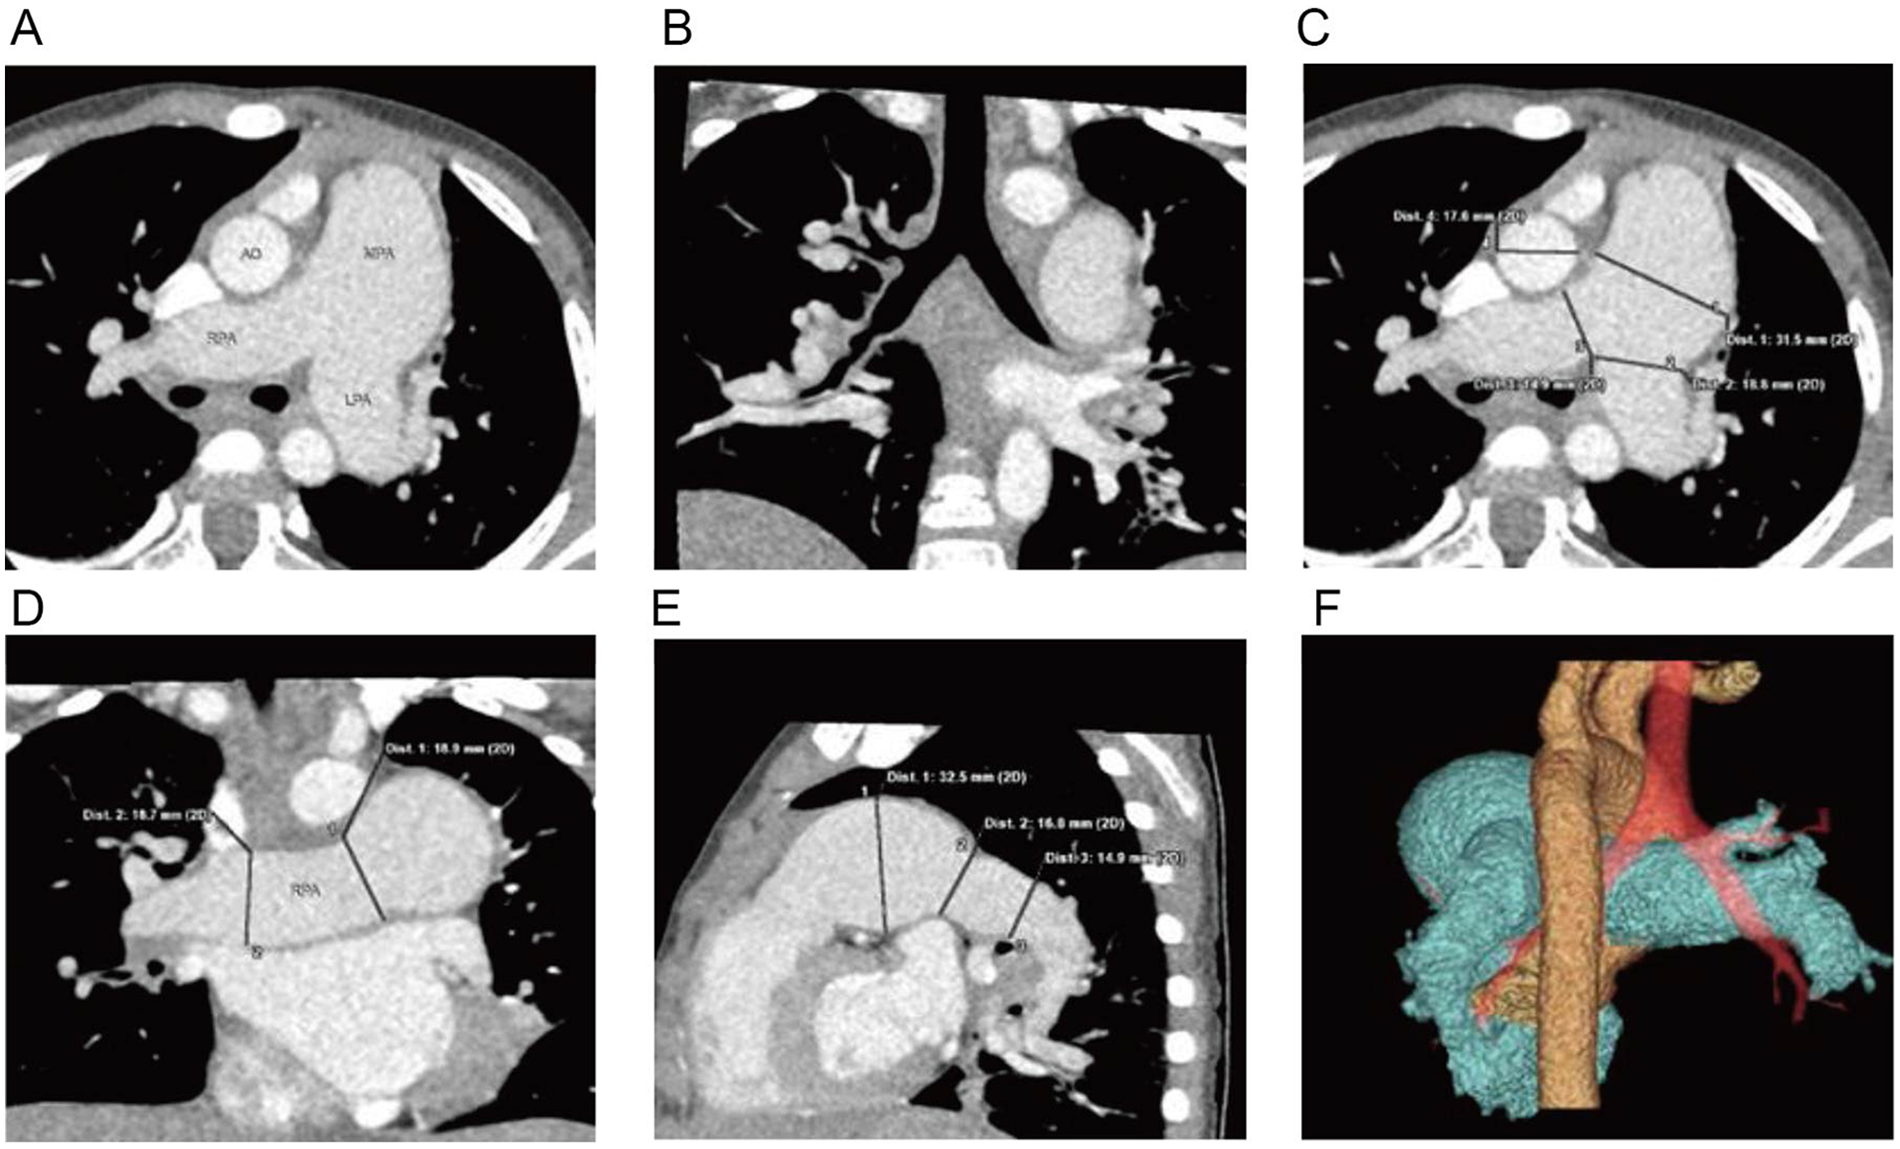

Electrocardiogram (ECG) was normal. Chest x-ray demonstrated normal lung markings and cardiac silhouette; however, the main pulmonary artery segment appeared prominently dilated. Given these findings and the need to assess for possible extracardiac vascular malformations, coronary computed tomography angiography (CCTA) was performed prior to echocardiography to obtain detailed three-dimensional visualization of the pulmonary artery and its branches. CCTA demonstrated significant dilation of the main pulmonary artery and its left and right branches (Figures 1A–1F) (4, 5).

Figure 1

Cardiac CTA: (A) significant dilation of the main pulmonary artery and its left and right branches, (B) coronal reconstruction reveals mild narrowing of the lumen of the right lower lobe bronchus, (C–E) three-dimensional reconstructions displaying the dilated main pulmonary artery and its left and right branches, (F) volume-rendered (VR) imaging providing a visualization of the relationship between the dilated pulmonary artery, aorta, and trachea.